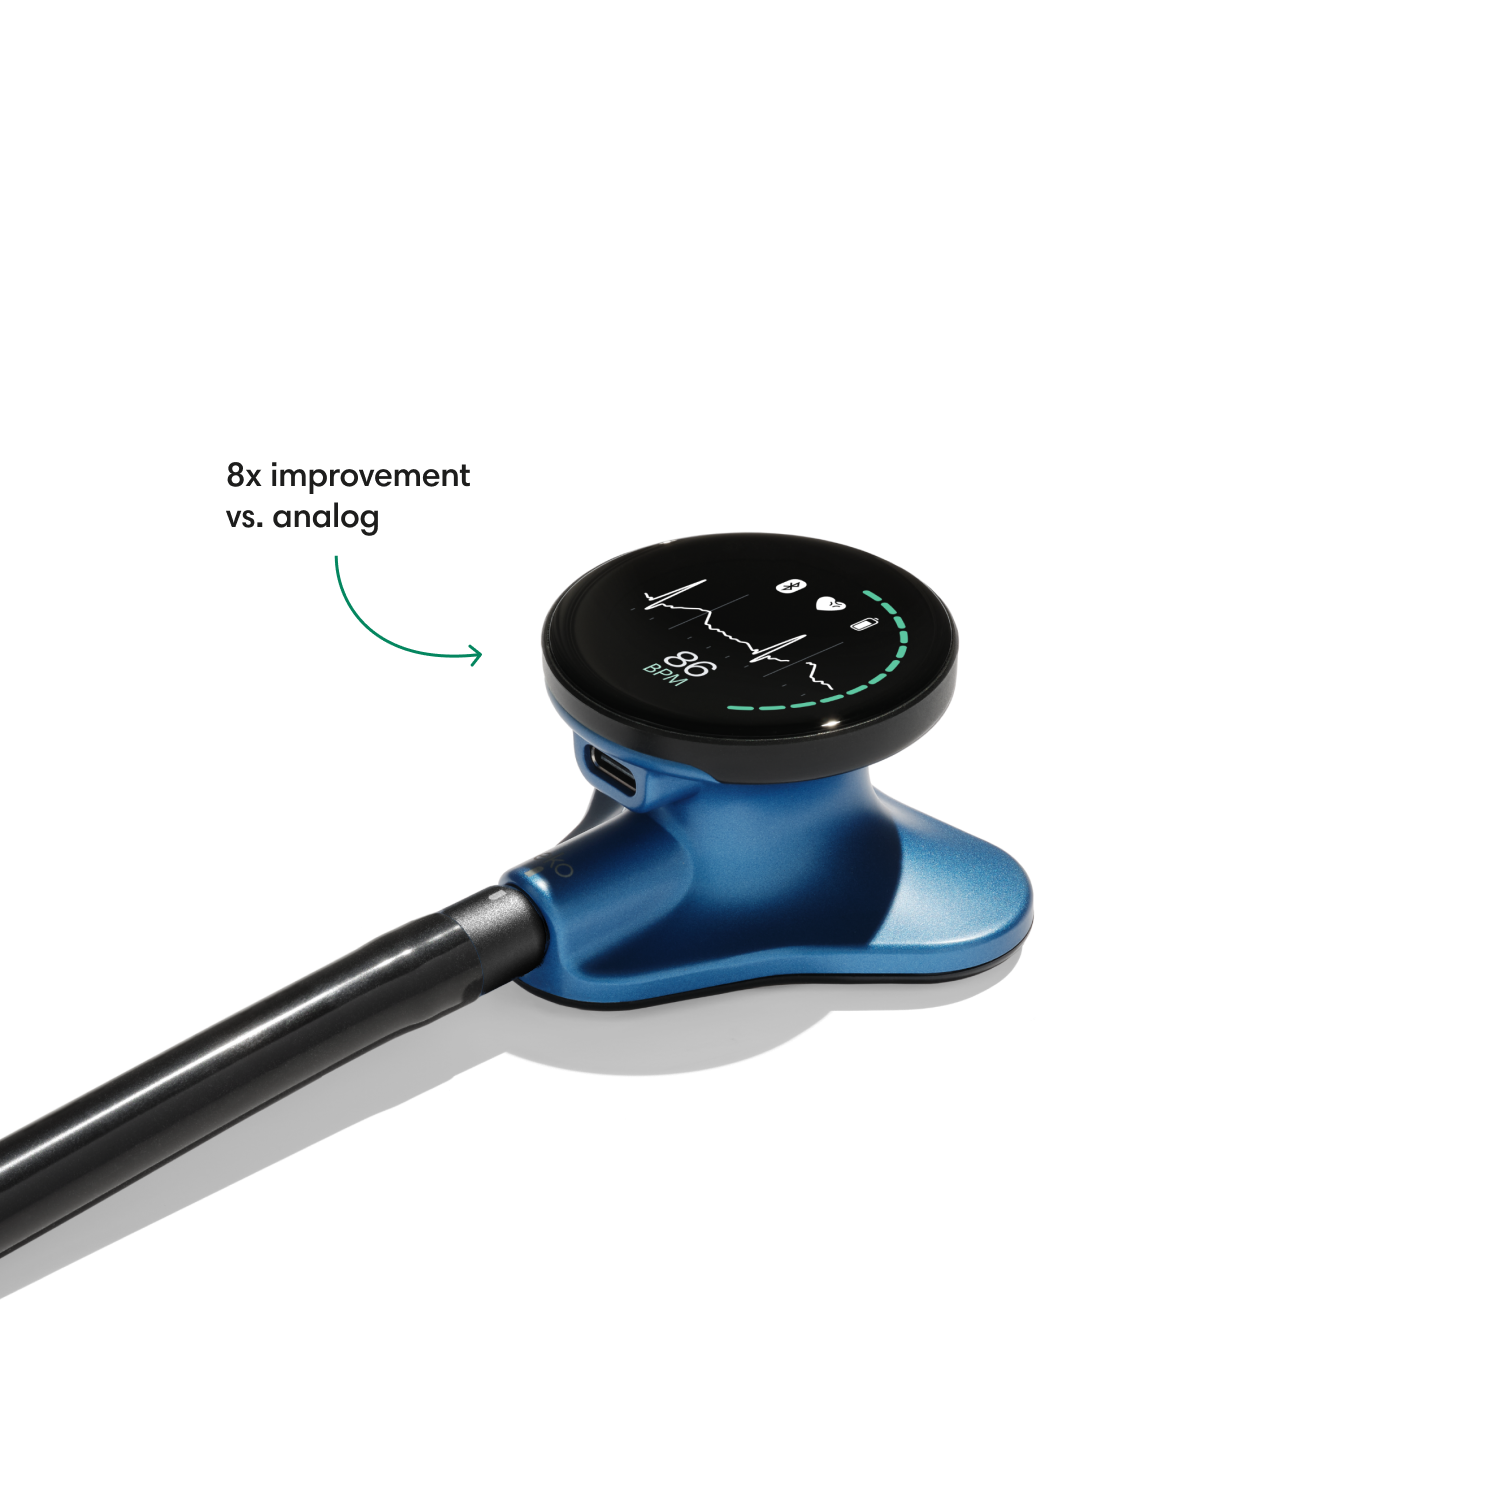

Instead of using a hollow tube like with an analog stethoscope, heart and lung sounds are delivered digitally through ear tip speakers. This results in unparalleled audio quality and sound cancellation.

- Reduces background noise 8x better vs. a typical analog stethoscope.